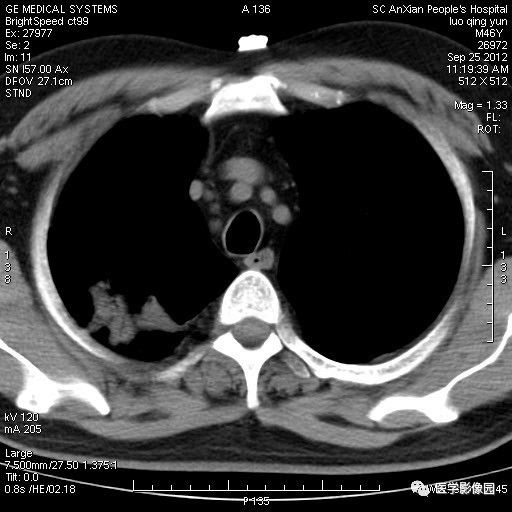

影像学表现:右上肺见不规则团块状高密度阴影,略有分叶级毛刺,边缘模糊,邻近胸膜增厚,增强扫描呈轻中度强化。

诊断结果:右上肺炎性假瘤

本病影像学表现无绝对特征性。单发多见,多位于肺表浅部位,多呈圆形或椭圆形,直径多在2-5cm或更大;多有假包膜,边缘多清晰光整,有时也毛糙,并可有分叶或毛刺;邻近胸膜局限性增厚、牵拉,病灶边缘呈桃尖样突起即桃尖征(尖端指向胸膜);增强扫描多呈中度均匀强化,持续时间较长。亦可显著强化。